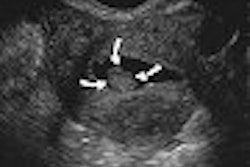

Siemens also showcased its new 8V3 Sequoia transducer for pediatric cardiology, which provides continuous focusing and image uniformity, broader bandwidth, and differentiation of near-field structures with higher resolution.

The company also demonstrated advancements in the Acuson CV70 cardiovascular system, such as its fourSight transesophageal view for integrated 3D imaging, and the new P9-4 transducer for pediatric cardiac imaging.